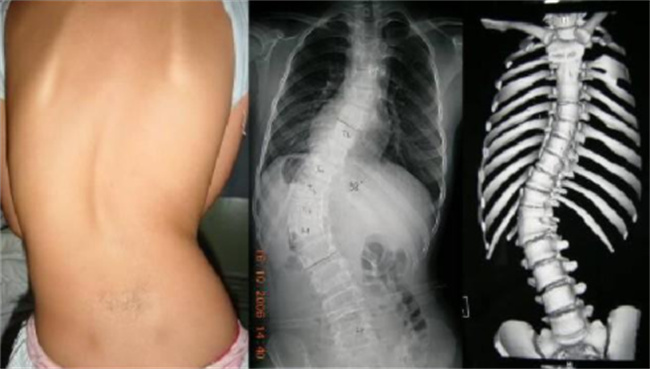

脊柱侧弯是指脊柱在横向方向上的弯曲,通常表现为肩膀、骨盆不平或倾斜等现象。脊柱侧弯的原因有很多,包括遗传因素、神经肌肉疾病、脊柱结构畸形等。接下来,我们将深入探讨导致脊柱侧弯的原因以及最有效的治疗方法。...

脊柱侧弯是指脊柱在横向方向上的弯曲,通常表现为肩膀、骨盆不平或倾斜等现象。脊柱侧弯的原因有很多,包括遗传因素、神经肌肉疾病、脊柱结构畸形等。接下来,我们将深入探讨导致脊柱侧弯的原因以及最有效的治疗方法。